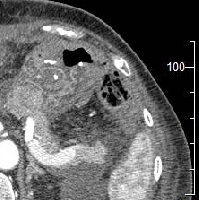

Πρόκειται για γυναίκα ασθενή 70 ετών, η οποία υποβλήθηκε σε αξονική τομογραφία για άτυπα γαστρεντερικά συμπτώματα, εμέτους και απώλεια βάρους. Διαπιστώθηκε συμπαγής μάζα του παγκρέατος, μεγέθους 3 εκατοστών, η οποία εντοπίζονταν στην κεφαλή του οργάνου και βρίσκονταν σε ικανή απόσταση από τα άνω μεσεντέρια αγγεία (εικόνα 1). Η ασθενής έλαβε 4 κύκλους προεγχειρητικής (neoadjuvant) χημειοθεραπείας (gemcitabine, cisplatine, erlotinib). Κατόπιν υποβλήθηκε σε επέμβαση Whipple's (εικόνα 2) με παγκρεατογαστροστομία (εικόνες 3, 4). Στο παρασκεύασμα (με και χωρίς αριστερή εκστροφή της χοληδόχου κύστης) φαίνεται η μάζα (εικόνες 5, 6).